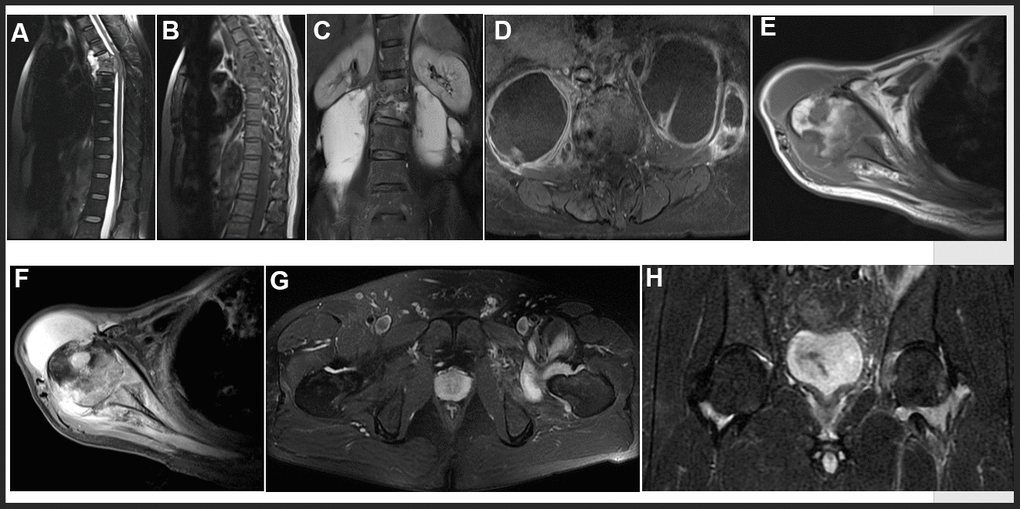

Diagnostic Values Of Peripheral Blood T Cell Spot Of Tuberculosis Assay T Spot Tb And Magnetic Resonance Imaging For Osteoarticular Tuberculosis A Case Control Study Aging